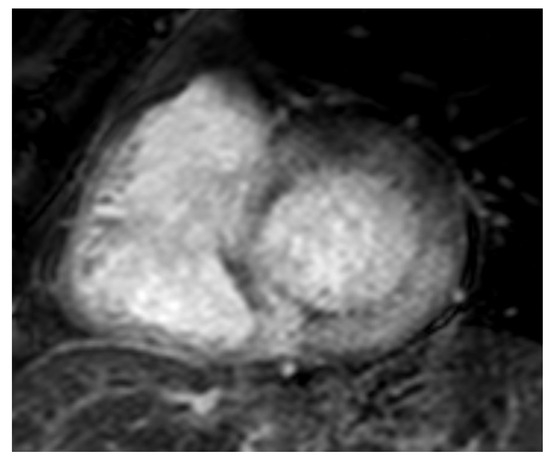

Figure 4.

AL 68-year-old patient diagnosed with endomyocardial biopsy. T1 scout sequence shows abnormal contrast agent kinetics (Dark blood pool signal).